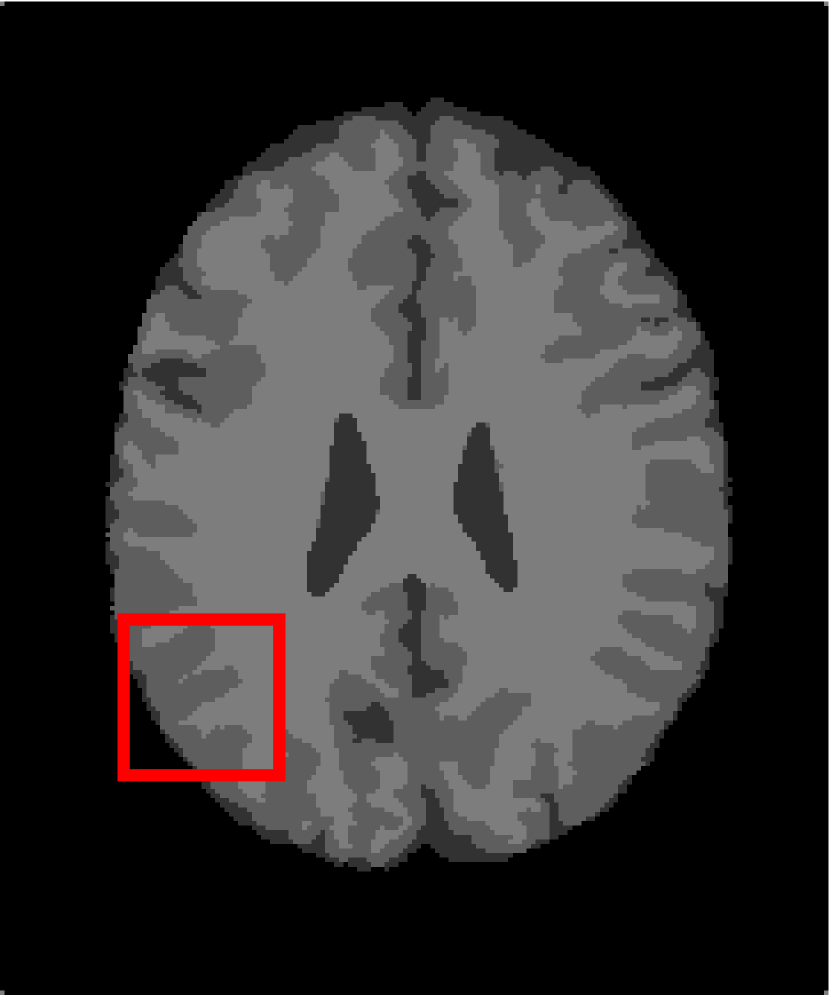

In the second experiments, we segment two medical images coming from a simulated brain database (BrianWeb): http://www.bic.mni.mcgill.ca/brainweb/. The two images are generated by T1 modality with slice thickness of 1mm resolution, 9% noise and 20% intensity non-uniformity. Here, the two images are represented two slices in the axial plane with the sequence of 100 and 110. Moreover, there are golden standard segmentations in the dataset. We set the numbers of clusters to 4. The visual comparisons are illustrated in Figs. 6 and 7.

Figure 7: Segmentation results for the second medical image. From (a) to (l): ground truth, noisy image and results of FCM_S1, FCM_S2, FGFCM, FLICM, KWFLICM, ARKFCM, FRFCM, WFCM, DSFCM_N, and LRFCM.

By focusing on the marked red square in Figs. 6 and 7, we easily find that FCM_S1, FCM_S2, FGFCM and ARKFCM are sensitive to noise. FLICM and KWFLICM are vulnerable to severe intensity inhomogeneity. FRFCM brings overly smooth results due to the use of gray level histograms. WFCM and DSFCM_N cause several contours to change. However, LRFCM acquires clear contours and suppresses noise adequately. Moreover, we find that the segmentation result of LRFCM is closer to ground truth.